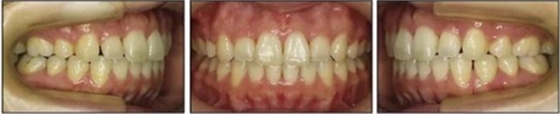

五、治療結(jié)果

治療后數(shù)據(jù)提示治療目標(biāo)達(dá)成。面相結(jié)果提示微笑及側(cè)貌得到改善(圖6)。達(dá)到了安氏I類尖牙關(guān)系和安氏II類磨牙關(guān)系,形成尖牙保護(hù)合。牙齒中線無偏斜,達(dá)到理想的覆合覆蓋,Spee曲線得到整平。

治療后頭側(cè)數(shù)據(jù)提示:無明顯骨性變化(上頜SNA82.1°,下頜SNB74.9°),上頜前牙得到內(nèi)收,略舌傾,頦部前后位置無明顯改變,仍未凸面型(圖8,表)。將治療前后圖像重疊后結(jié)果如(圖8及圖9),24月后隨訪結(jié)果見圖10.